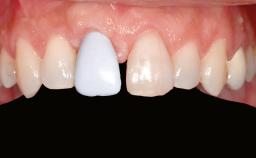

Her chief complaint was her inability to masticate efficiently due to the recent loss of her mandibular second premolars and first molars bilaterally. She expressed a desire for fixed prostheses in the shortest possible time due to her advanced age, requesting that replacement teeth should look as natural as possible. She was otherwise comfortable and not experiencing any symptoms from her teeth.

Patient's Esthetic Expectations Low Medium High

Esthetic Risk Low